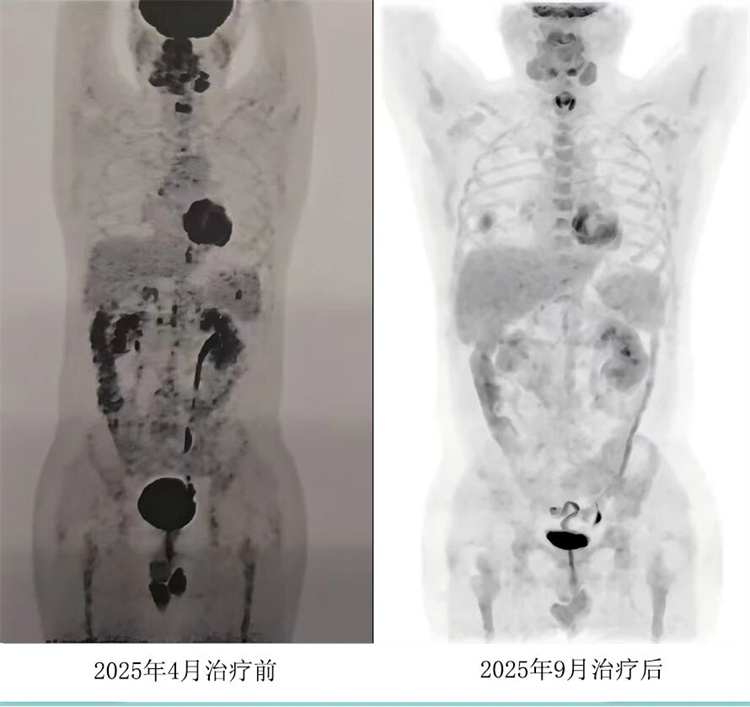

病例匯報(bào)環(huán)節(jié)由我院淋巴瘤科張薇醫(yī)生帶來了三例精彩紛呈的難治復(fù)發(fā)彌漫大B淋巴瘤CAR-T治療的病例。

病例過程跌宕起伏,從橋接治療到靶點(diǎn)的選擇,并發(fā)癥的處理都極具代表性。張醫(yī)生詳盡分享了患者在治療過程中的挑戰(zhàn)、決策依據(jù)以及CAR-T細(xì)胞治療后的驚人緩解與轉(zhuǎn)歸,充分展示了CAR-T技術(shù)為晚期患者帶來的突破性生存希望。